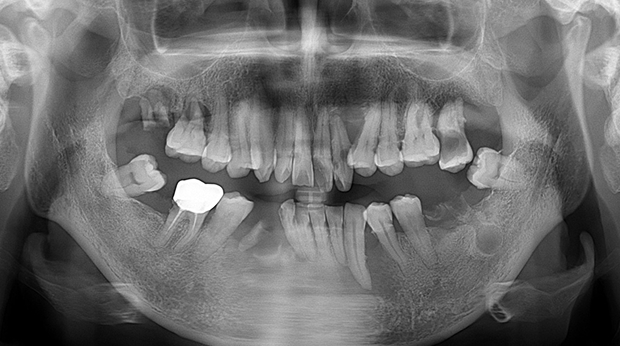

구강외과 진료

매복 사랑니 발치

의식하진정법(수면마취)/임플란트

임플란트와 사랑니 발치는 외과적 시술로 잇몸을 절개하는 외과적 시술은

짧으면 짧을 수록 시술 후 붓기와 통증이 최소화됩니다.

치과의사 경력 14년차 구강외과 전문의가 빠르고 안전하게, 아프지 않게 수술해 드립니다.